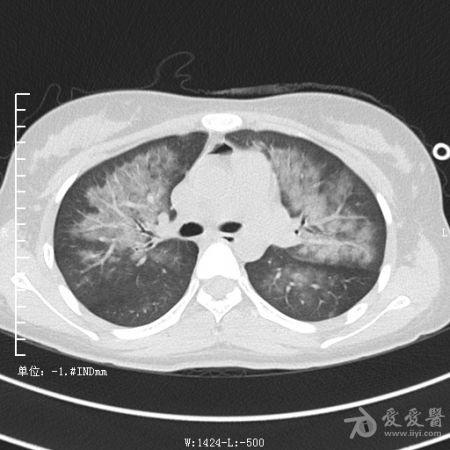

典型支气管扩张及肺水肿CT片

典型支气管扩张肺水肿